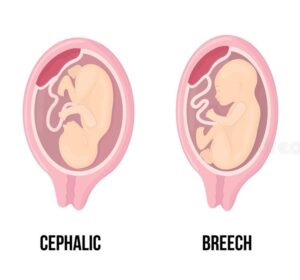

Your baby’s position inside the uterus is called their fetal position or fetal presentation. The ideal position is a Cephalic Presentation which means that the baby’s head is down. The most common form of Cephalic Presentation is the Vertex Presentation which is referring to the crown of the baby’s head leading into the birth canal path.

If your baby is not in a Cephalic/Vertex Presentation, your baby is considered Breech, meaning your baby’s butt is down, not the head. There are a couple variations within the Breech position as well.